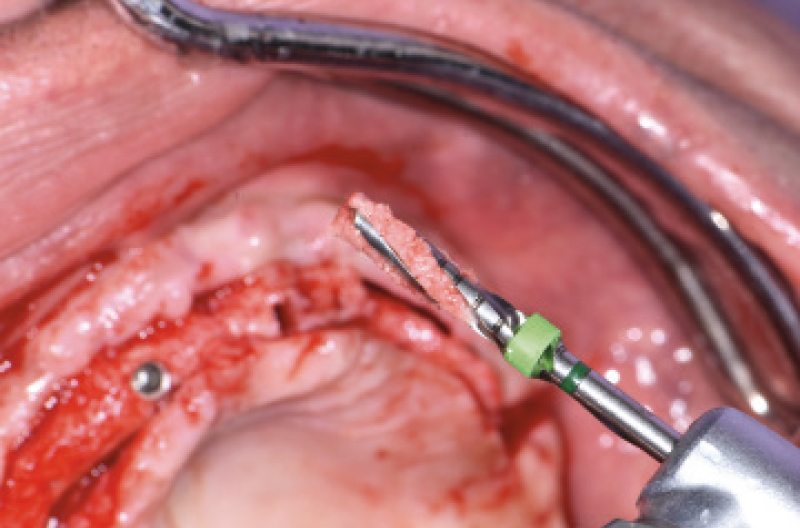

Nel mese di luglio 2019 il paziente ├© stato operato con il contestuale inserimento di 10 impianti, 4 nellŌĆÖarcata inferiore e 6 nellŌĆÖarcata superiore. Ho inserito 4 impianti Max Stability ├ś 3,75 mm nella zona della premaxilla, uno lungo 10 mm e gli altri tre da 12 mm di lunghezza; in regione 15 e 25 ho dovuto invece utilizzare delle frese da osseodensificazione per compattare lŌĆÖosso e traslare la parete mediale del seno mascellare per poter inserire 2 impianti Max Stability ├ś 3,75 L 12 mm inclinandoli lungo la parete stessa. Data la scarsa quantit├Ā e qualit├Ā di osso nel mascellare, ho rinunciato al carico immediato rinviando la procedura della protesizzazione immediata nella fase di riapertura degli impianti ad osteointegrazione avvenuta (Figg. 1-14).

Fig. 9 – Osseodensificazione e traslazione parete mediale del seno mascellare di destra